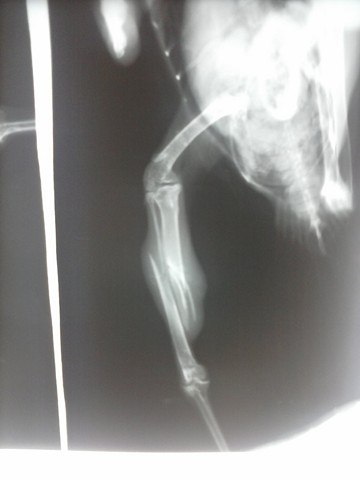

• У вороши перелом берцовой кости со смещением.

Сделан рентген в ЦВК, показана операция остеосинтеза.

26.06.12г. проведена операция, прогноз осторожный.

• Птишк уже после операции - на снимке видно внешнюю